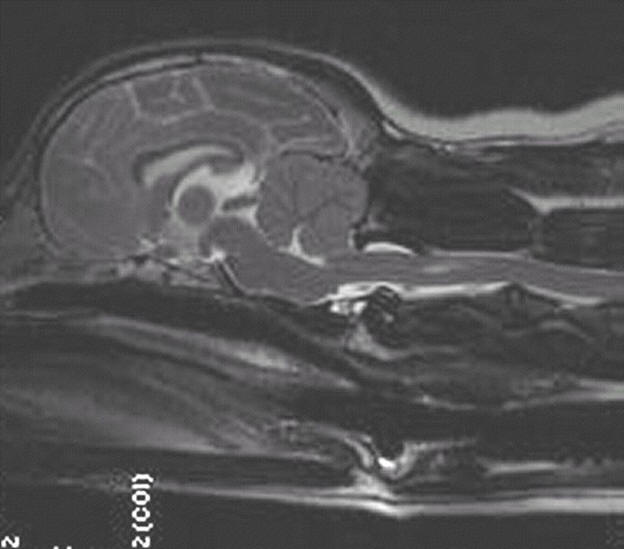

2 years old

Had SM symptoms and has since had surgery

Moderate malformation/squashing of

cerebellum

Herniation of cerebellum

Medulla kinked/squashed

Large syrinx starting just beyond C1